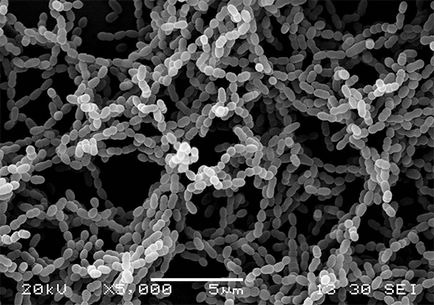

Az eredmény a tevékenység a baktériumok Streptococcus mutans és néhány kilátás nyílik a plakk felületi képződik a szerves savak, megjelenő miatt enzimatikus bontását maradékok szénhidrát, mint a cukor. Ezek a savak ok „kimosási” fő ásványi komponensek egy kristályrácsba zománc (kalcium, fluor, foszfor).